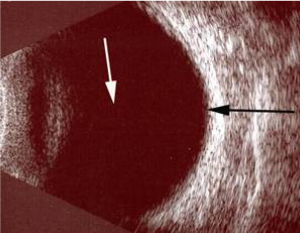

Resim 1: Normal göz ultrasonu görüntüsü. Beyaz ok göz sıvısını (vitreus) , siyah ok retina tabakasını göstermektedir.

Göz ultrasonu, gözün ön bölümündeki kesiflikler nedeniyle retinanın muayene sırasında seçilemediği durumlarda, tanının belirlenmesi ve tedavi planlanması aşamasında, göz içi lensi, vitreus ve retinanın incelenmesini sağlayan, çok önemli bir görüntüleme yöntemidir. Ultrasonografide ses dalgalarının değerlendirilmesi ve bu ses dalgalarının intraoküler dokular tarafından yansıması prensibi kullanılır.

Göz ultrasonu asıl olarak iki ana durumda kullanılır. En önemli kullanım alanı matur kataraktı olup da arkası görülemeyen hastalar da katarakt cerrahisi düşünülüyorsa arkada ki retinanın değerlendirilmesi için kullanılır. Ayrıca göz içinde kanama var ise ve retina net seçilemiyorsa retina hakkında bilgi verir. Ağrısız bir yöntem olup herhangi bir ilaç yada boya verilmez.